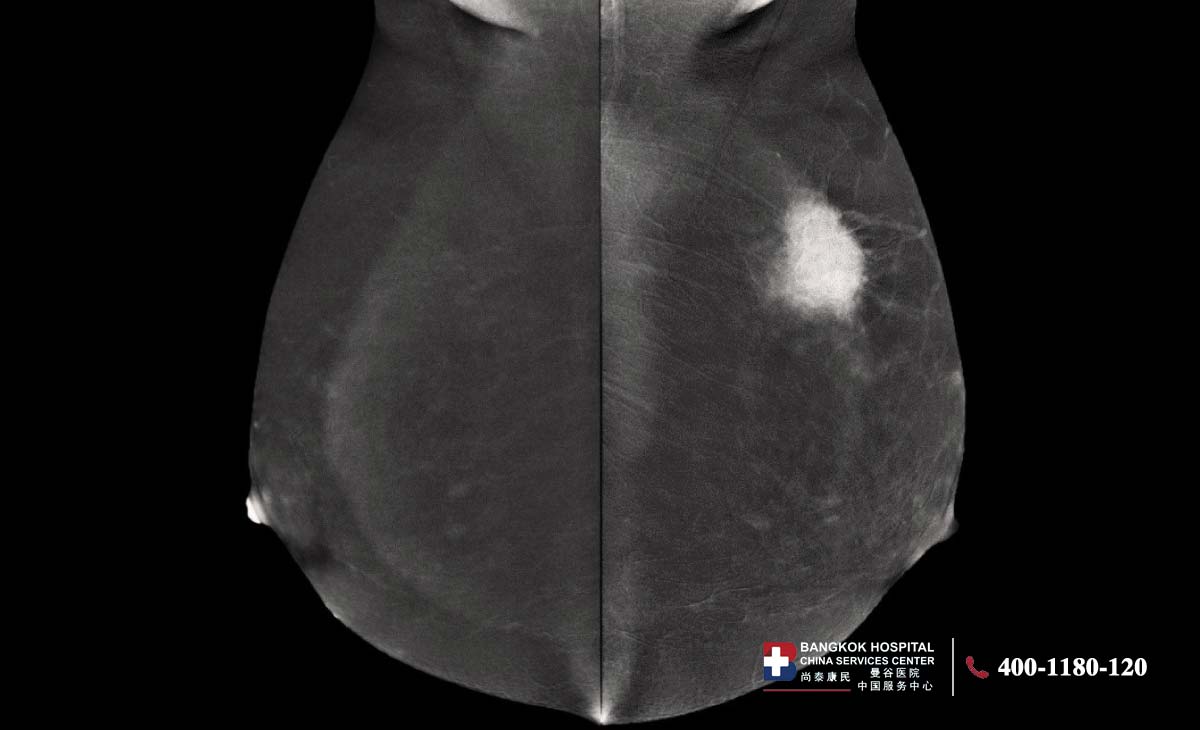

对比增强乳腺X线摄影(CEM)自2011年起获得美国食品药品监督管理局批准上市。大量研究证实了该技术的临床应用价值,其在国际上的应用也日益广泛。该检查需注射含碘对比剂,并采用双能X线成像技术对乳腺进行数字化X线摄片。设备会分别采集低能和高能两种能量下的影像,再经处理生成重组图像。这项技术能够清晰显示乳腺组织中的可疑病灶,提示可能存在的异常血供或乳腺癌病变。CEM在成像原理上与乳腺磁共振(MRI)相近,相较于常规乳腺X线摄影准确性更高,尤其适用于乳腺致密型人群。

曼谷癌症医院乳腺中心、乳腺影像诊断专家Dr.Khwansakul Boonsararuxapong表示,CEM是一种结合造影剂和乳腺X光的影像检查技术。检查时医生会先注射造影剂,再通过双能量X光成像,让乳腺中的异常血管或可疑病灶更加清晰地显示出来。